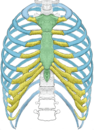

What is this muscle

The levator scapulae